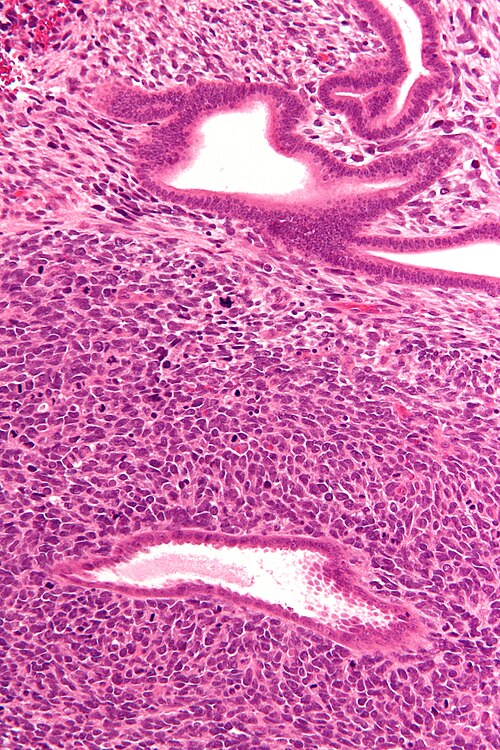

Provided clinical history

55 year old woman, uterine bleeding, polypoid mass

Site

Uterus

Primary image

Low magnification. H&E stain.